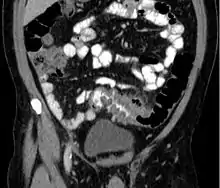

عادةً يتم تشخيص من يعانون من الأعراض المذكورة أعلاه بواسطة التصوير المقطعي المحوسب [6] حيث تصل درجة دقّته إلى 98% في تشخيص التهاب الرُّتوج، للحصول على أهم المعلومات الممكنة الموضِّحة لحالة المريض يتم أخذ صور لطبقات رقيقة تصل(5 ملم) لكامل البطن والحوض في وسط تبايني من خلال اعطاء المريض الصبغة التباينية عن طرق الفم والوريد. من خلال الصور يتم ملاحظة زيادة موضعية في سُمك جدار القولون وكذلك التهابات تمتد إلى النسيج الدهني الحيط به.[7] التهاب الرُّتوج الحاد يتم تشخيصه بدقة عندما يشمل الجزء المعنيّ على رتج أو جيب.[8] كما يتم من خلال التصوير الطبقي أو المقطعي تحديد المرضى الذين يعانون من التهابات مضاعفة كوجود الخُراج حيث يسمح بتصريفه كذلك فيتم تجنيب المريض التدخل الجراحي الفوري. لا يستخدم تنظير القولون أو حقنة الباريوم في حالات الالتهاب الحاد تجنباً لخطورة حدوث انثقاب بالقولون.